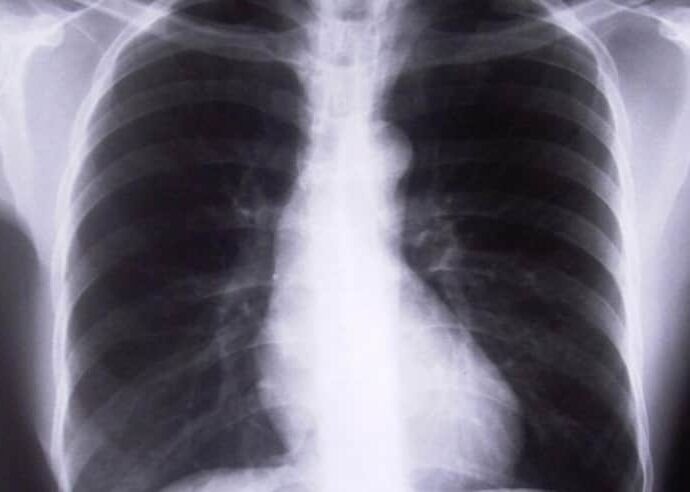

Сигнали, алармиращи за рак на белия дроб

Има признаци, по които може да определите развиващото се заболяване Но има признаци, по които можете да определите развиващото се заболяване. Някои от симптомите са продължителна и упорита кашлица (две до три седмици), която се отбелязва при 50–75% от пациентите, хемоптиза, болка в гърдите. Също така трябва да обърнетеВиж още